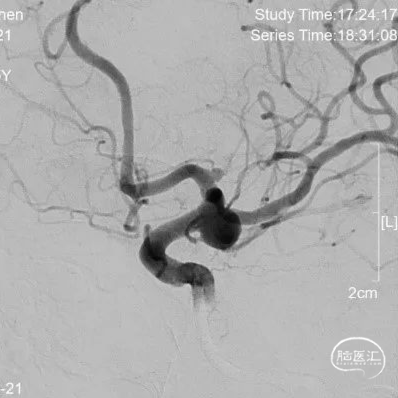

DSA:后交通动脉瘤(瘤体6.7mmx5.6mm,瘤颈5.2mm)合并A1起始部微小动脉瘤(瘤体1.7mmx1.9mm,瘤颈1.7mm)且指向后方。

左侧后交通动脉瘤破裂出血

左侧A1起始部微小动脉瘤